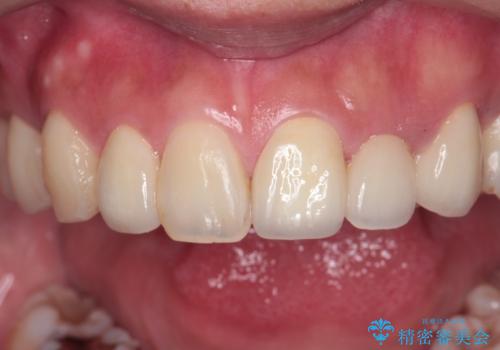

前歯の審美的なブリッジ (歯列矯正後)

- 66万円 内訳:ジルコニアクラウンブリッジ(スペシャル) 15.4万円×4本、仮歯 1.1万円×4本費用は治療当時の料金となります

矯正治療で歯の位置を整えてからブリッジを入れると歯の幅を自由に設定できるため、左右対称にできます。結果矯正なしでいきなりセラミックにする場合と異なり、無理に角度を変えたりする必要がなく、神経をなるべく温存したまま審美的なセラミック治療が行えます。

セラミック治療の注意事項(リスク・副作用など)

- 天然歯を削ります

- 硬い素材は天然歯を傷つけてしまう場合があります

- かみ合わせや歯ぎしりが強すぎる方はセラミックが割れてしまう可能性があります

- 自費診療(保険適用外治療)となります